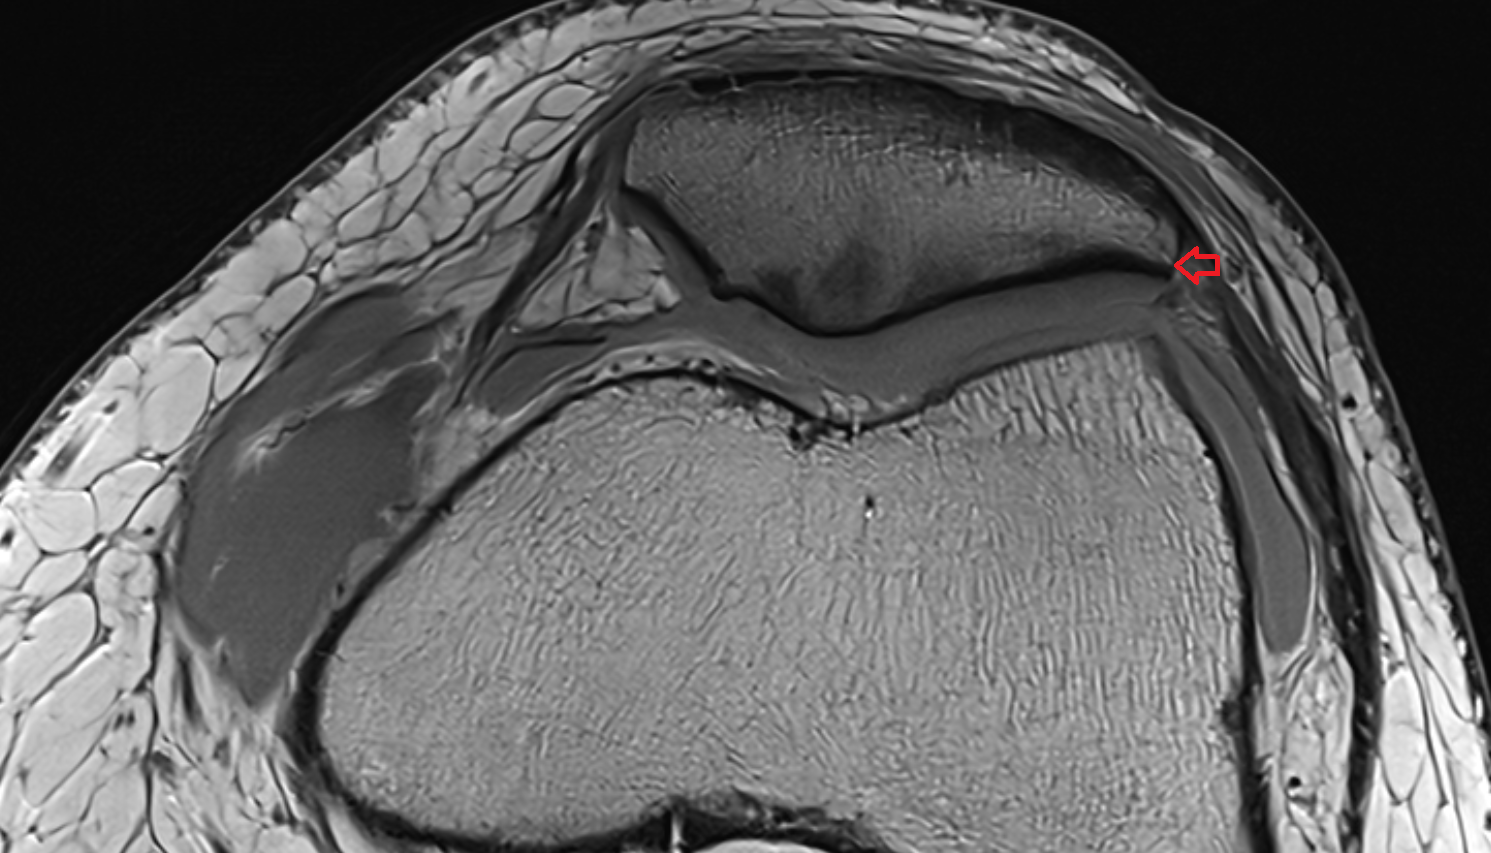

- Medial meniscus

- Lateral meniscus